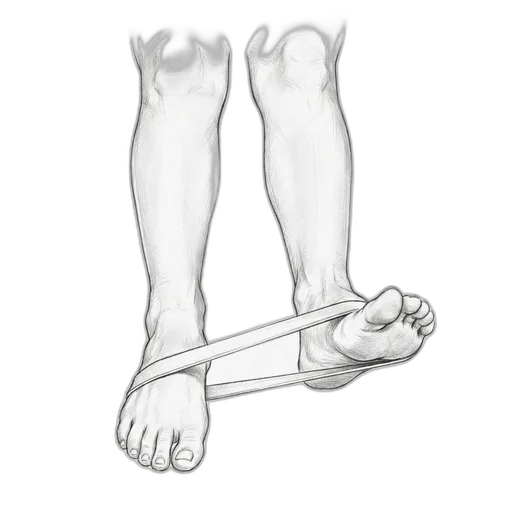

Resistance Band Eversion

This exercise strengthens the peroneal muscles — the muscles on the outside of your lower leg that prevent your ankle from rolling inward. Think of them as your ankle's natural brace. After a sprain, these muscles often weaken and their reflexes slow down, which is a big reason why people re-sprain the same ankle. Resistance band training rebuilds that strength and re-trains the "catch reflex" that protects you.

What to expect: By several weeks, your ankle should feel noticeably more stable during walking and on uneven surfaces. Strength testing typically shows meaningful improvement by 6 weeks. The real win: a significantly lower chance of re-spraining your ankle — studies show up to 50% reduction in re-injury with consistent peroneal training.

How to do it: Sit with your legs out in front of you. Loop a resistance band around the ball of your foot and anchor the other end to something sturdy (a table leg works well) or your other foot. Slowly turn the sole of your foot outward against the band's resistance, then return slowly. Keep your knee still — the movement should come from your ankle, not your leg.

| Mild | 2 sec at end range | 15 | 3 | 1×/day | Use a medium band. Go slow: 3 seconds out, 2-second hold, 3 seconds back. Control matters more than speed |

| Moderate | 2 sec at end range | 10 | 2 | 1×/day | Use a light band. Slow and smooth — don't let the band snap your foot back |

| Severe | 1 sec at end range | 8 | 1 | every other day | Use the lightest band you can find. Stay in a pain-free range. If your ankle swells after, ice it and rest a day |

How to progress: Light band → medium → heavy. Once eversion is solid, add inversion (turning inward) and dorsiflexion/plantarflexion (up and down) to work all four directions. The ultimate progression: standing on one leg while doing band work.

⚠ When to skip this: Wait at least 72 hours after an acute ankle sprain before starting. Don't do this if you have a peroneal tendon that's subluxing (popping out of its groove) — that needs to be addressed first. Post-surgical: wait until Dr. Patish clears you.